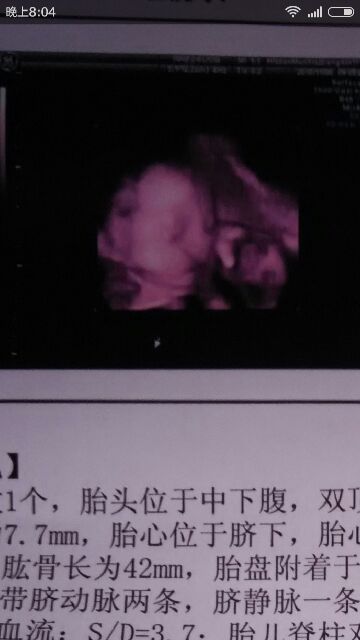

目前想起这么多,宝妈有疑问的能够回复问我,下面是我两个月,四个月,还有六个月的B超单!